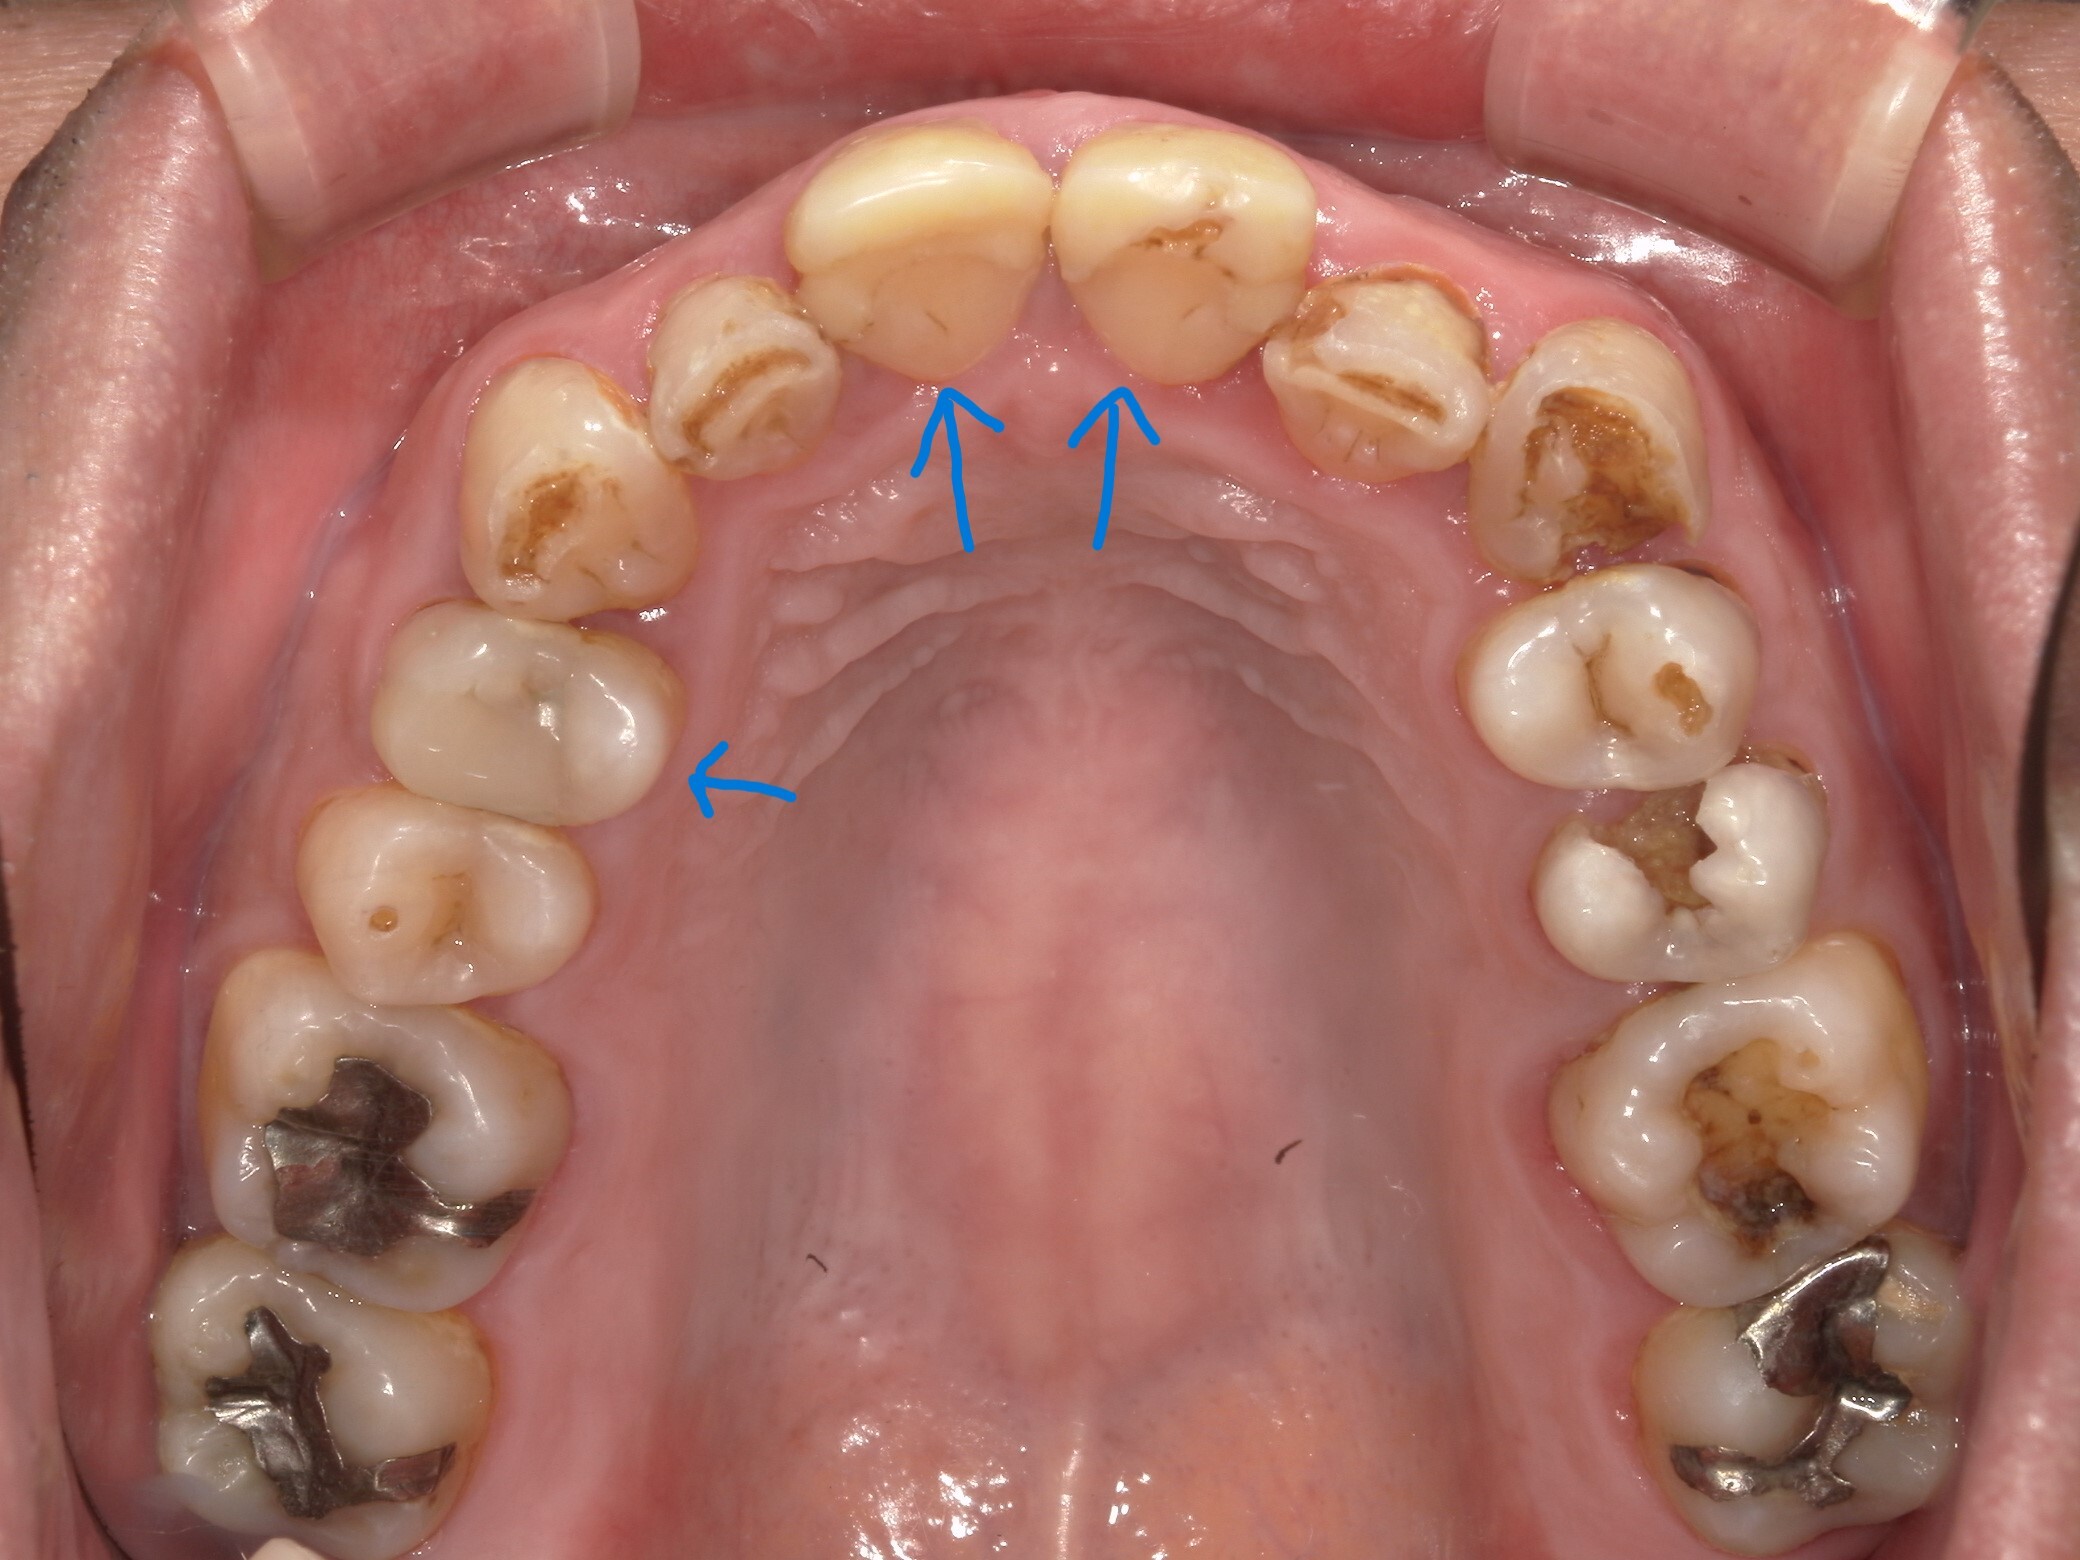

ドックベストセメント治療の問題点

先日3例目のドックベストセメント治療を受けた酸蝕歯の患者さんが何回通院しても治らないということ...

ドックベストセメント治療の失敗

先日2例目のドックベストセメント治療でトラブルになった患者さんが来院された。 写真の右下7番は...

ドックベストセメント治療の被害

最近、ドックベストセメントによる治療のトラブル例が増えています。 写真はドッグベストセメント治...